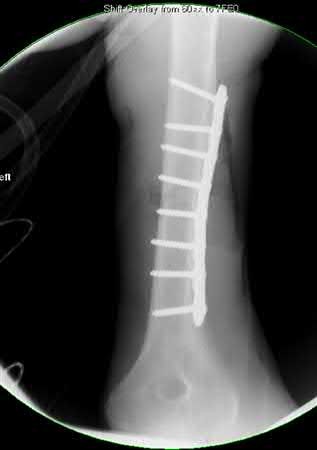

A 64-year-old woman is thrown off a horse, sustaining the injury shown in Figures A and B. She undergoes surgical fixation as seen in Figures C through E. What is the most commonly reported complication of this procedure?

The patient in the scenario has a 2-part proximal humerus fracture treated with a locking plate as seen in Figures A-E. The most common complication with the use of this implant is screw penetration. The terms screw cut out and penetration are often used interchangeably in the literature with cut out appearing more frequently in reports regarding intertrochanteric fractures.

Owsley et al retrospectively reviewed 53 proximal humerus fractures treated with locking plates and the same post-operative protocol. The most common complication was screw cut out or penetration, followed by varus displacement. They concluded that 3 and 4-part fractures in patients over 60 years have a higher incidence of failure.

Agudelo et al retrospectively reviewed 153 patients at a level-one trauma center treated with proximal humerus locking plates, investigating modes of failure for the implant. They determined that varus malreduction (head-shaft angle